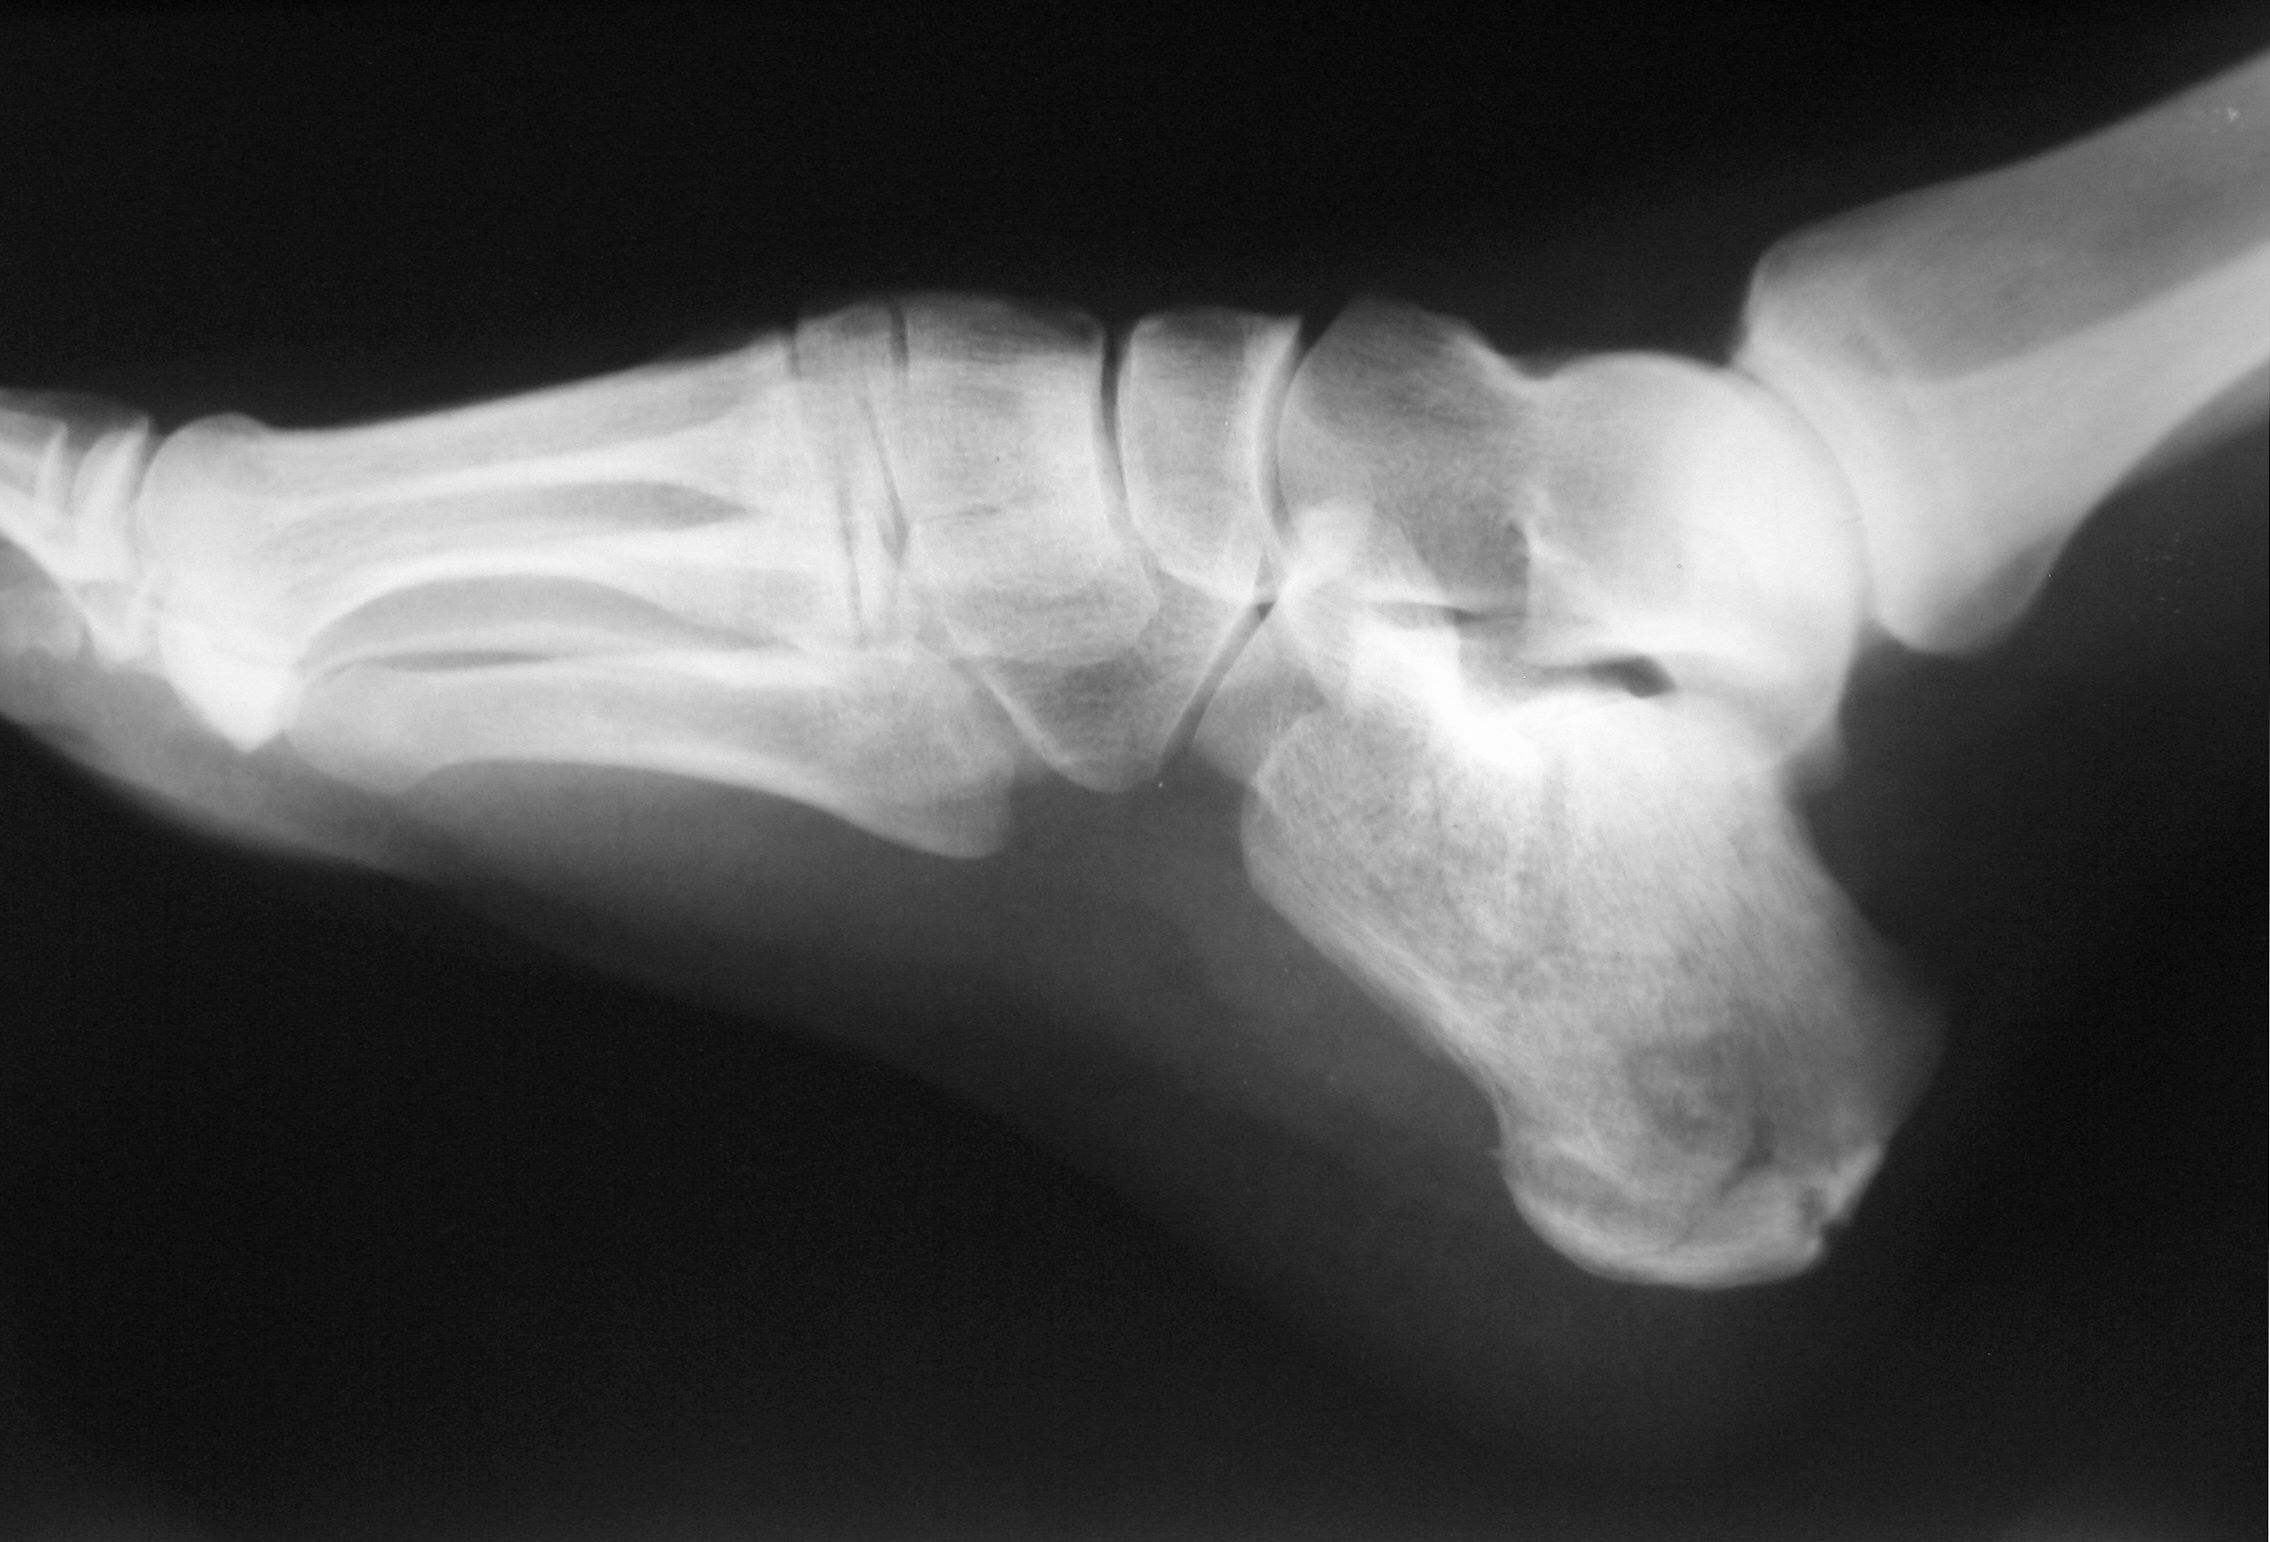

인간의 발꿈치뼈는 발목뼈 중 가장 크고 발에서 가장 큰 뼈이다. 발꿈치뼈의 긴 축은 앞쪽과 가쪽을 향한다.[3]

목말뼈, 발꿈치뼈, 발배뼈는 발목뼈의 몸쪽 열을 구성하는 뼈로 간주된다.[2] 발꿈치뼈에서는 몇 가지 중요한 구조를 구별할 수 있다.[2]바닥면의 뒤쪽에는 큰 '''발꿈치융기'''가 있으며, 가쪽과 안쪽 결절이 있다. 가쪽 표면에는 종아리뼈 결절이 또 하나 있다.[3] 양쪽 아래쪽 가장자리에는 가쪽 및 안쪽 돌기가 있는데, 이는 엄지 벌림근과 새끼 벌림근의 기시 부위 역할을 한다. 아킬레스건은 위쪽의 거친 부위에 삽입되며 입방뼈는 앞쪽 면과 연결된다. 위쪽 면에는 목말뼈와의 관절을 위한 세 개의 관절면이 있다.[3] 이 위쪽 관절 사이와 목말뼈의 해당 부위 사이에는 '''발목굴'''(뼈사이 목말발꿈치 인대가 위치한 통로)이 있다. 발꿈치뼈의 안쪽 표면 위쪽과 앞쪽 부분, 중간 목말 관절면 아래에는 수평 돌출부인 '''목말 지지대'''가 있다.[3] 목말 지지대는 바닥쪽 발꿈치발배(용수철) 인대, 정강발꿈치 인대, 그리고 안쪽 목말발꿈치 인대에 부착된다. 이 돌출부는 위쪽으로는 오목하며 목말뼈의 중간 발꿈치 관절면에 연결되고, 아래쪽으로는 긴 엄지 굽힘근의 힘줄이 지나가는 홈이 있으며, 앞쪽 가장자리는 바닥쪽 발꿈치발배 인대에 부착되고, 안쪽 가장자리는 발목 관절의 세모 인대의 일부에 부착된다.

가쪽에는 일반적으로 '''발꿈치 결절'''(또는 도르래 돌기)이라고 하는 결절이 있다. 이것은 긴 종아리근과 짧은 종아리근의 힘줄 사이에 위치한 솟아오른 돌출부이다. 이는 발꿈치뼈 가쪽 표면의 두 개의 사선 홈(종아리 근육의 힘줄을 위한)을 분리한다. 그 주요 해부학적 의미는 이전에 긴 종아리근과 짧은 종아리근의 먼쪽 힘줄이 공유하던 일반적인 경로가 각기 다른 부착 부위로 가는 도중에 갈라지는 지점이라는 것이다.[2]

발꿈치뼈는 두 개의 관절, 즉 몸쪽 발목뼈 사이 관절과 목말발꿈치 관절의 일부이다. 발꿈치뼈의 끝부분은 발꿈치 활액낭으로 덮여 있다.

2. 2. 관절

발꿈치뼈는 발목뼈 중 가장 크고 발에서 가장 큰 뼈이다. 발꿈치뼈에서는 몇 가지 중요한 구조를 구별할 수 있다.[2]발꿈치뼈는 두 개의 관절, 즉 몸쪽 발목뼈 사이 관절과 목말발꿈치 관절의 일부이다. 발꿈치뼈의 끝부분은 발꿈치 활액낭으로 덮여 있다. 위쪽 면에는 목말뼈와의 관절을 위한 세 개의 관절면이 있다.[3] 이 위쪽 관절 사이와 목말뼈의 이에 상응하는 부위 사이에는 '''발목굴'''(뼈사이 목말발꿈치 인대가 위치한 통로)이 있다. 발꿈치뼈의 안쪽 표면 위쪽과 앞쪽 부분, 중간 목말 관절면 아래에는 수평 돌출부인 '''목말 지지대'''(''''sustentaculum tali''')가 있다.[3] 목말 지지대는 위쪽으로는 오목하며 목말뼈의 중간 발꿈치 관절면에 연결되고, 아래쪽으로는 긴 엄지 굽힘근의 힘줄이 지나가는 홈이 있으며, 앞쪽 가장자리는 바닥쪽 발꿈치발배(용수철) 인대에, 안쪽 가장자리는 발목 관절의 세모 인대의 일부에 부착된다.